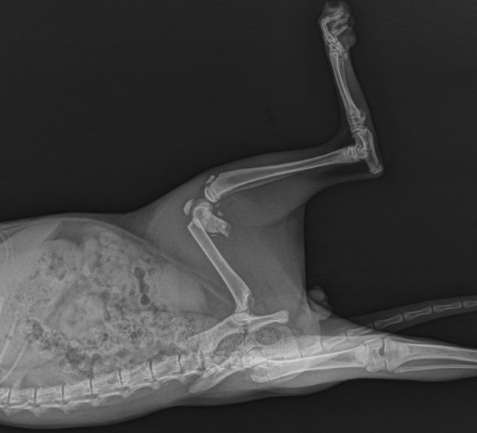

- X-ray(필수), 필요 시 CT/MRI(관절·성장판·척추/신경 평가)

- 수술적 치료: 변형·불안정·분쇄·개방·성장판/관절내 골절 →

- 핀/와이어(수내정)

- 플레이트 & 스크류(미니플레이트 포함)

- 외고정 장치(ESSF) 등